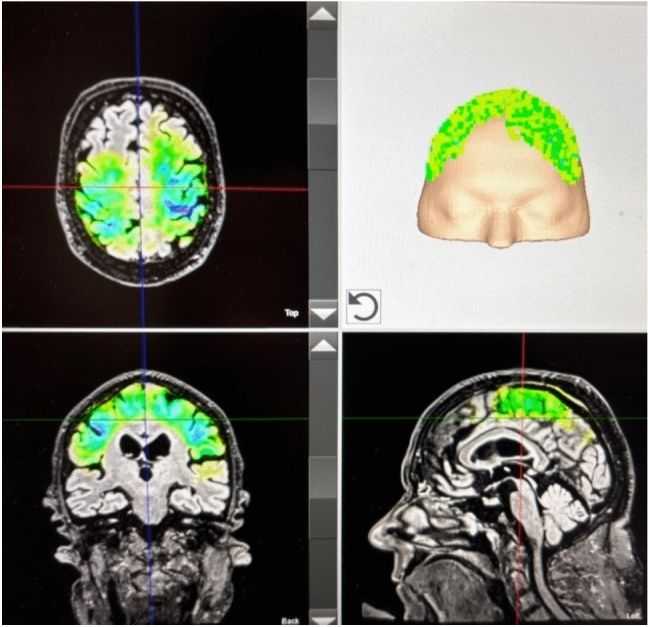

- w neurologii i psychiatrii (przezczaszkowa stymulacja impulsowa, TPS)